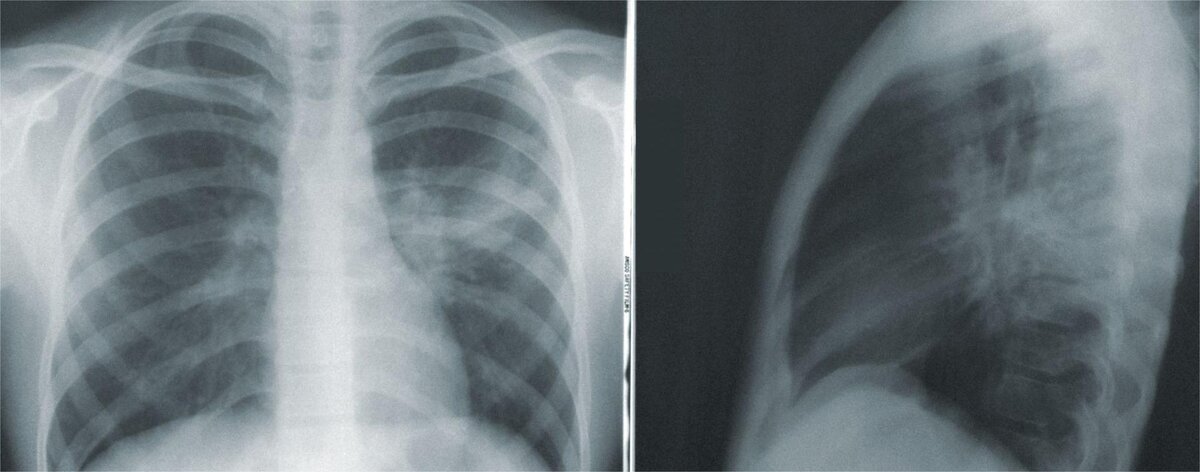

Рентгенография

Рентген грудной клетки и флюорография — 0,03 мЗв.

Рентгенография и флюорография отлично подходят в качестве скрининга заболеваний в связи с маленькой нагрузкой и простотой выполнения. Чаще всего рентген является первой ступенью диагностики, чтобы без необходимости не превышать установленную нормами лучевую нагрузку на организм.